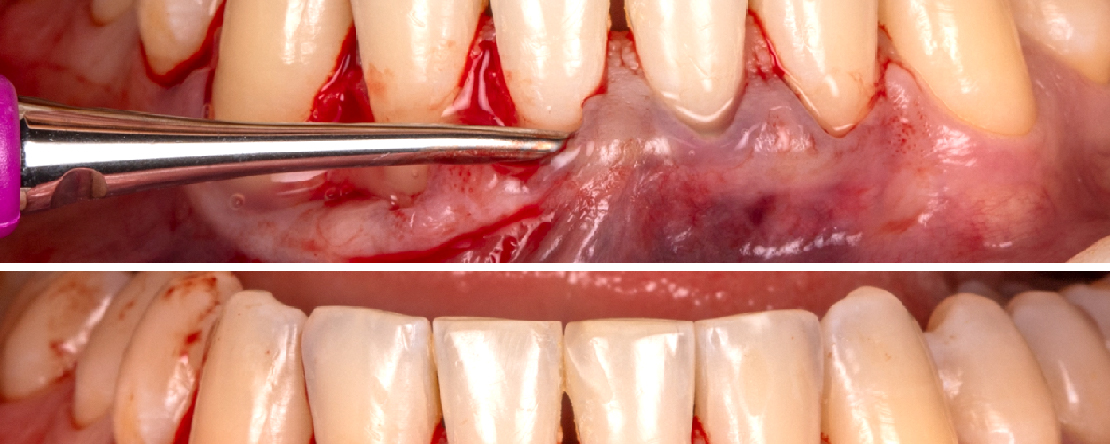

A cirurgia plástica periodontal engloba procedimentos ressectivos relacionados sobretudo com técnicas de aumento de coroa clínica, bem como procedimentos reconstrutivos, como a recuperação da gengiva queratinizada perdida ou o recobrimento radicular de recessões gengivais.

A cirurgia plástica periodontal tem vindo a desenvolver-se e a tronar-se cada vez mais previsível à medida que a microcirurgia se tem consolidado também, neste campo cirúrgico.

Nesta formação pretende-se atualizar os conceitos e técnicas de microcirurgia periodontal, bem como mostrar as indicações e vantagens de cada uma delas quando aplicadas aos problemas estéticos periodontais que se nos apresentam no dia-a-dia clínico.